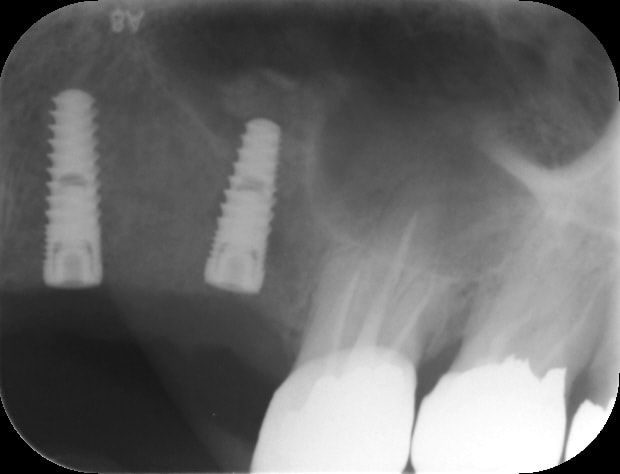

21/03/2017 à 18h57

par contre je fais pas mal de radios, exemple spreaders trop près de la racine donc changement d'axe (d'où l’intérêt de l'expansion)

016 gn9x9q - Eugenol

013 r6cbqu - Eugenol